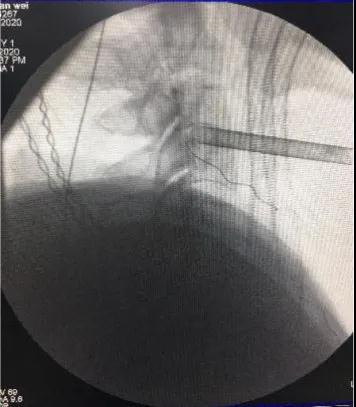

颈后路术术中套管定位

颈前路术术中套管定位